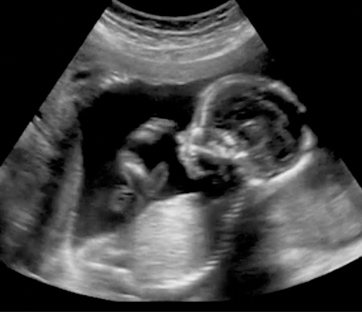

Molti i progressi compiuti negli ultimi anni: si parla ormai di ecografia 4D, di risonanza magnetica fetale per individuare eventuali anomalie del feto, di  comparazione quantitativa del Dna (Array – Comparative Genomic Hybridization) che si effettua quando il bambino è affetto da una malformazione. Ma è in particolare su due nuove tecniche che si concentra oggi l’attenzione. Si tratta dei test di screening prenatale non invasivi (“Non Invasive Prenatal Test” – Nipt) su Dna fetale circolante e della diagnosi genetica preimpianto (Pgd) che si effettua sull’embrione in caso di fecondazione in vitro.